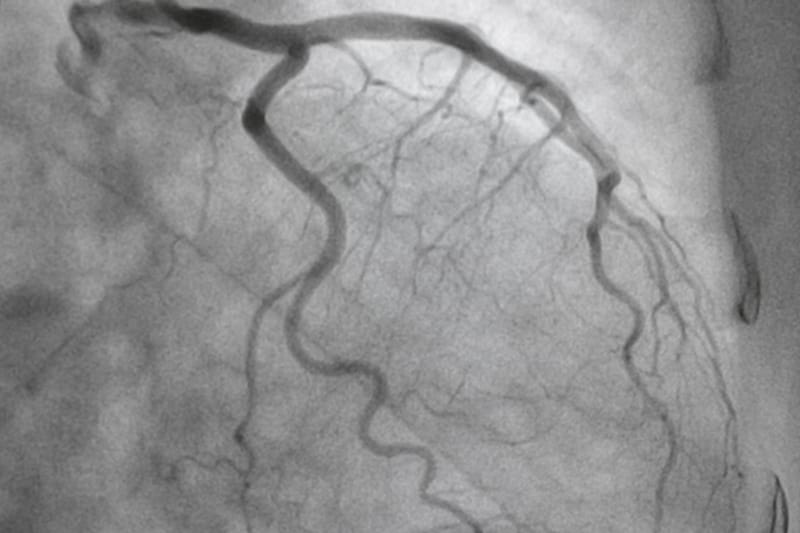

Dr Cuneyt Ada's expertise is coronary angiography and stent insertion. Dr Ada uses cutting-edge imaging technology to personalise each patient's stenting procedure in order to improve long-term outcomes. He regularly gives lectures to local and international cardiologists and is one of Australia's leading experts in the field.

Angiography Angioplasty Stenting (PCI) Coronary Physiology Intracoronary Imaging CTO PCI